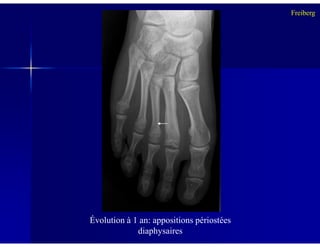

-- appositions périostées diaphysaires réactionnelles pfappositions périostées diaphysaires réactionnelles pf

Évolution à 1 an: appositions périostées

diaphysaires